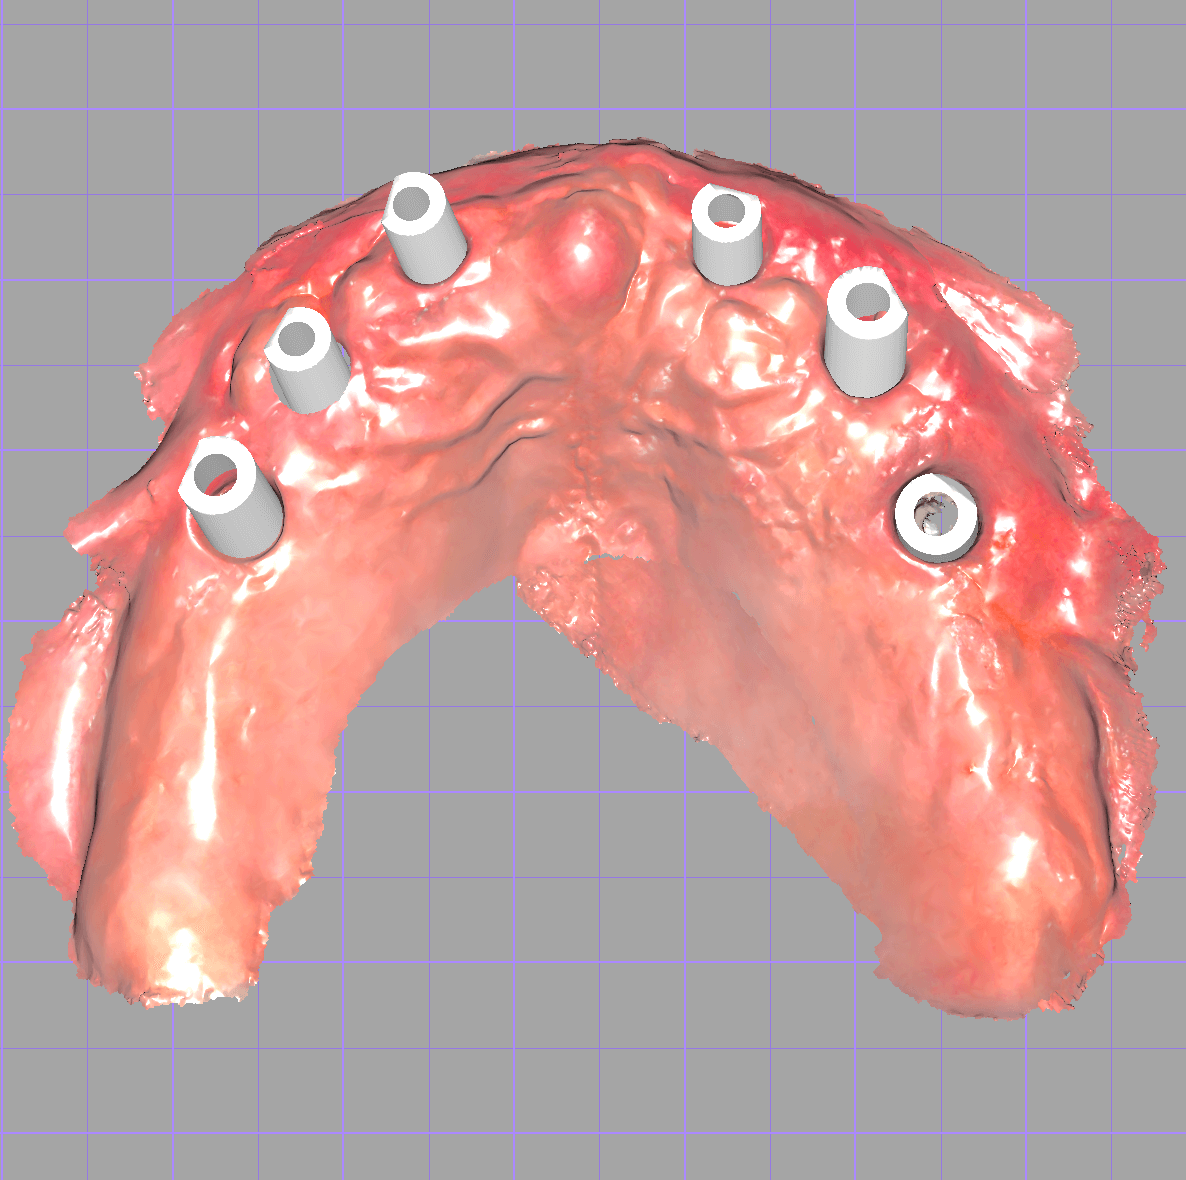

Pro otiskování implantátů se používají skenovací tělíska, která zajišťují přesné určení pozice a sklonu implantátů.

Na co se zaměřit

Především pahýly a aproximální plochy sousedních zubů musí být naskenovány naprosto přesně. Jsou zásadní pro správné dosednutí a kontakt náhrady.

Skenujte vždy celou čelist

Otisk musí vždy obsahovat celou čelist, i když je náhrada jen v části oblouku. Jen tak můžeme zajistit přesnou artikulaci a přirozenou funkci zubů.

CAD technik si stáhne všechny soubory do exocadu

CAD modelace testovací verze

CAD modelace

CAD technik vytvoří kompletní zubní náhradu v plně anatomickém tvaru včetně zubů.